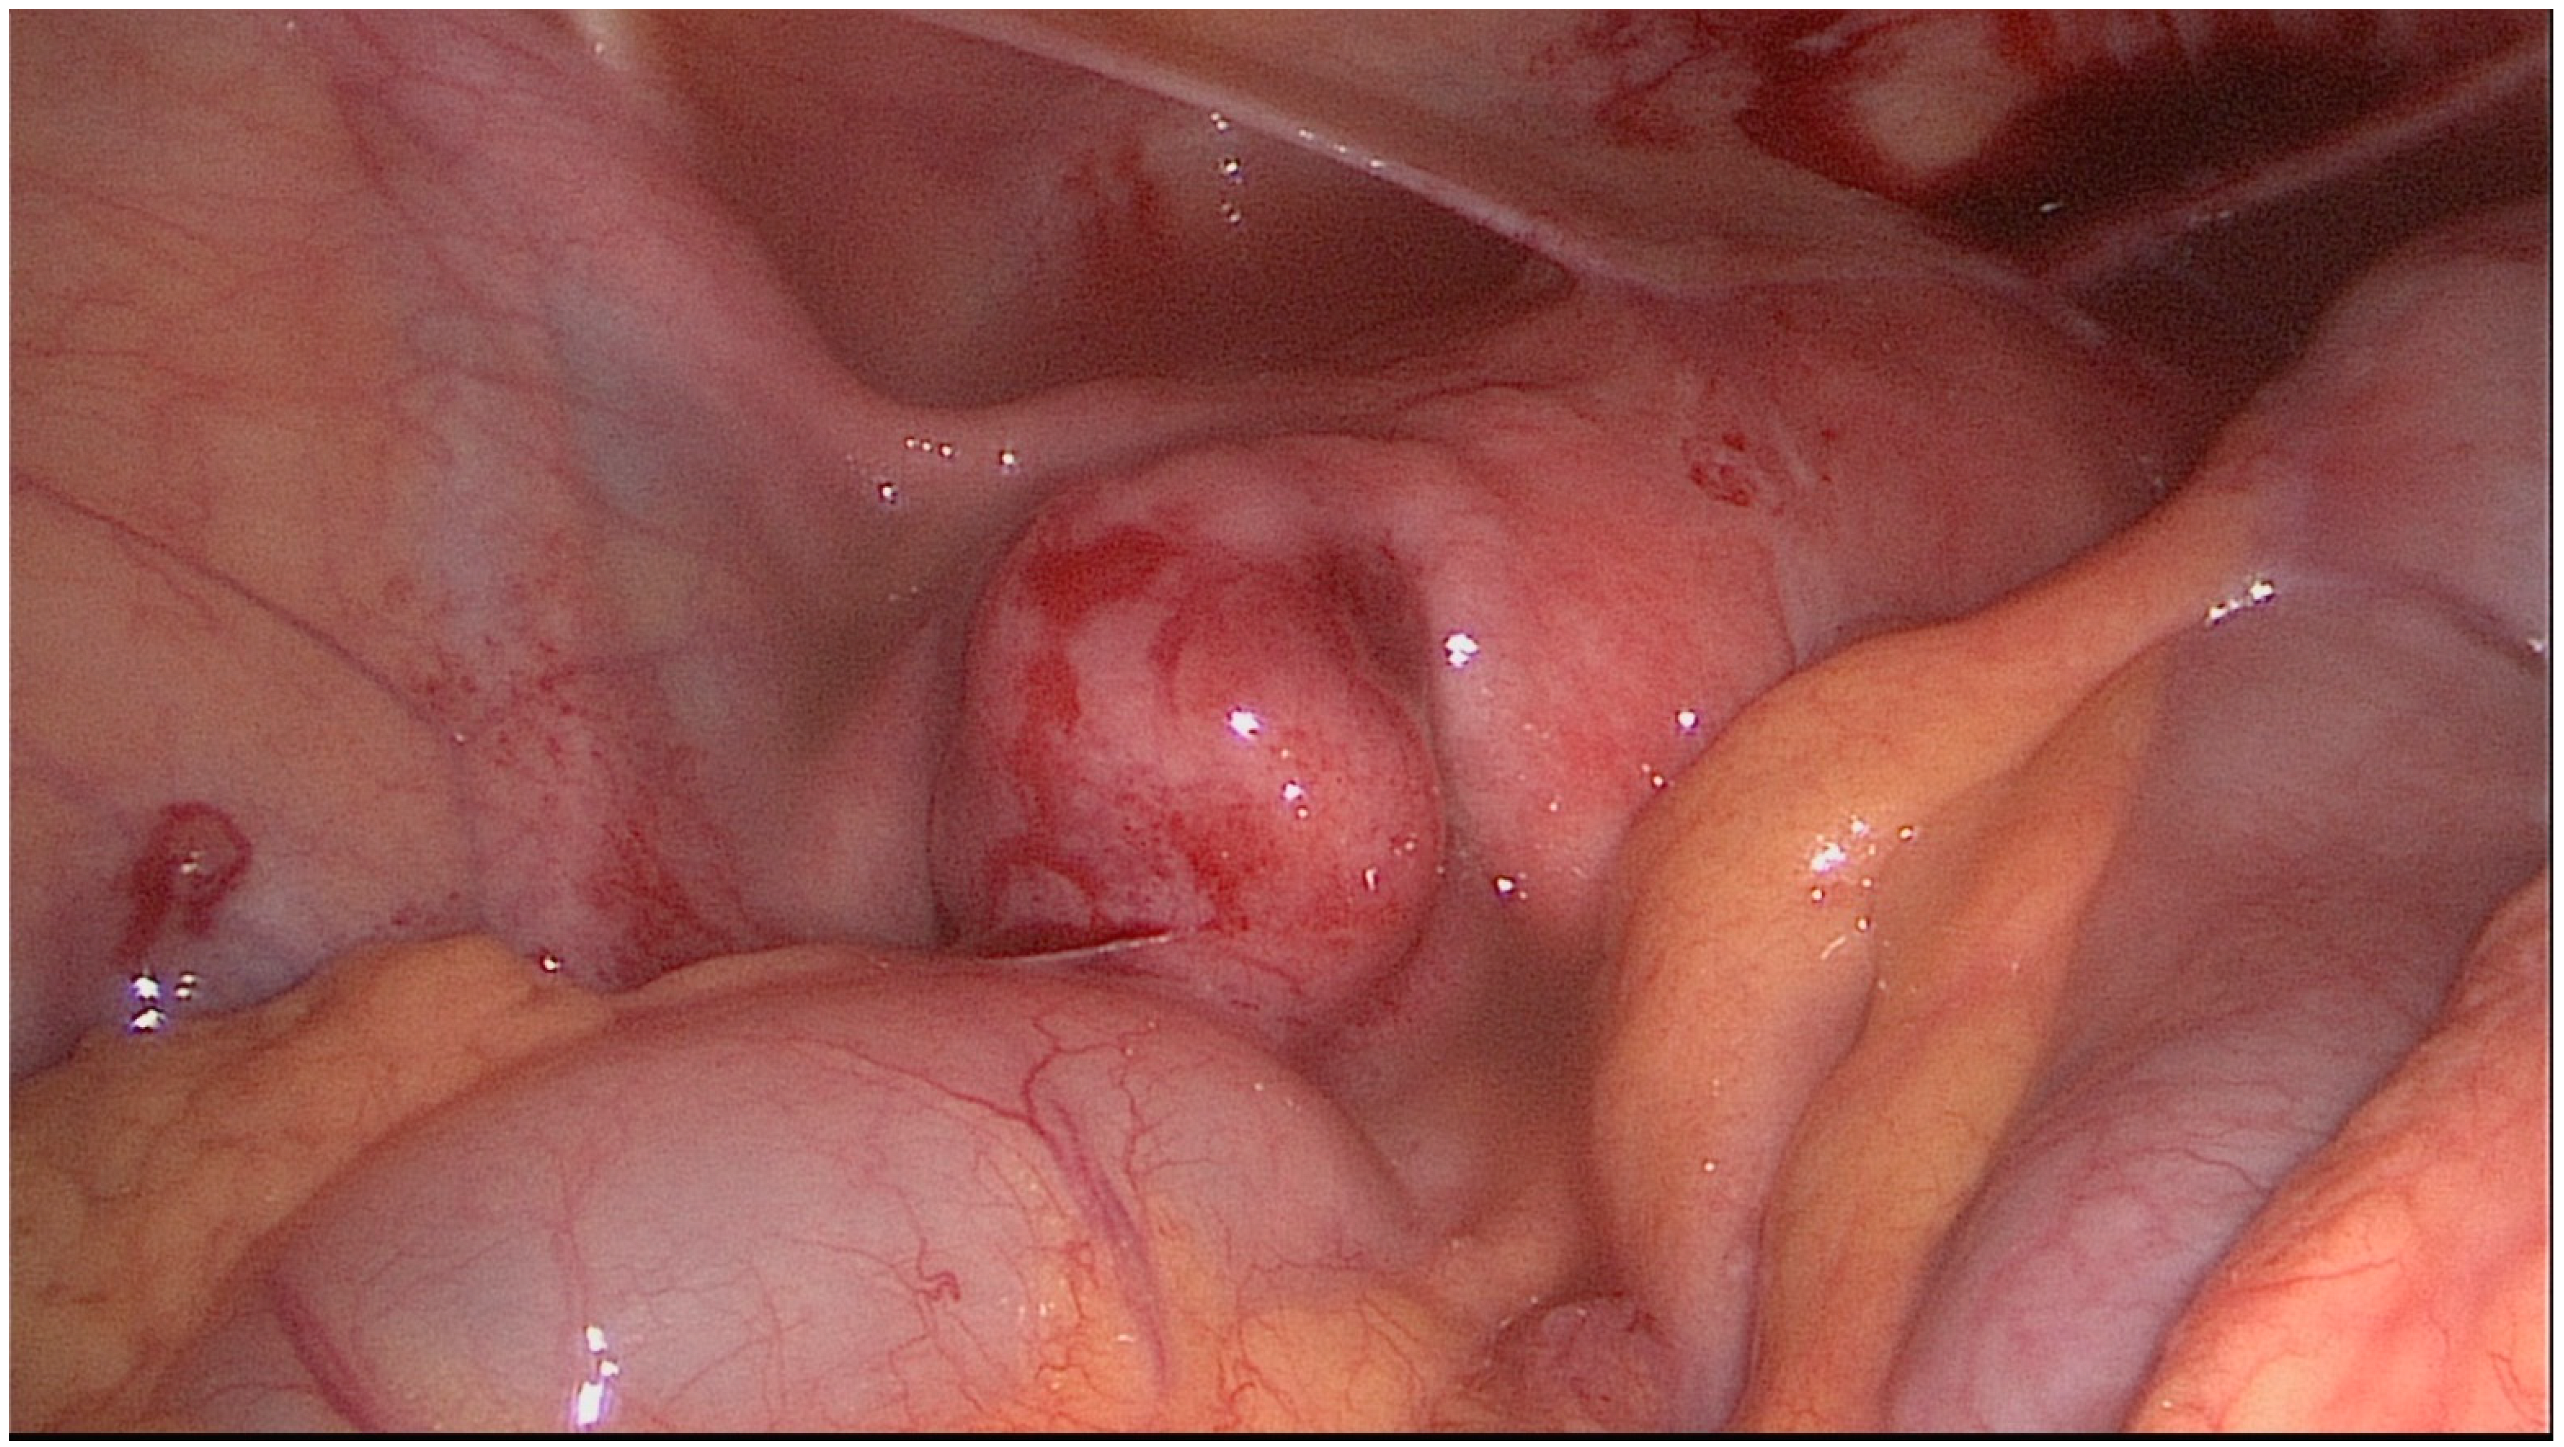

3. Treatment Strategy and Decision-Making Process

4. Operative Techniques in Reconstructive Distal Tubal Surgery